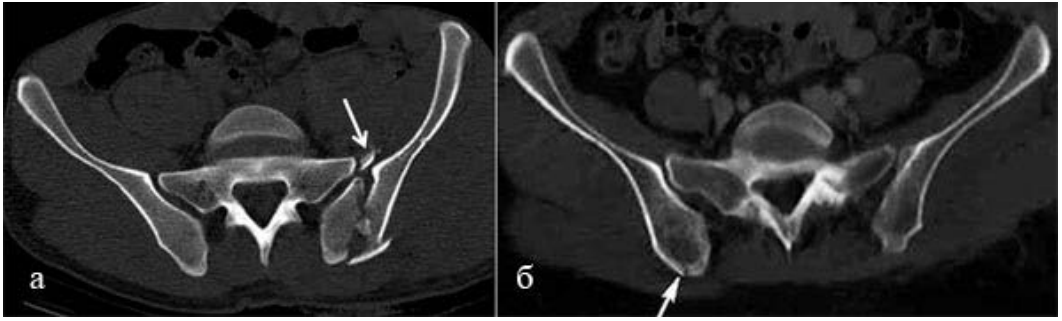

В рамках настоящего исследования изучены и проанализированы данные, полученные при лучевых методах исследования у 15 ВИЧ-инфицированных пациентов с гистологически верифицированным диагнозом плазмобластная лимфома, проходивших лечение в период с 2014 до 2023 г. в гематологическом отделении Сургутской окружной клинической больницы. В своем исследовании мы получили данные, которые не противоречат обзорам других исследователей. Плазмобластная лимфома развивается у лиц 40–50 лет, злокачественная лимфома впервые диагносцируется на III или IV стадии согласно шкале Анн-Арбор. Для нее характерно поражение ротовой полости, однако нередки случаи поражения желудочно-кишечного тракта. Данный вид лимфомы в 83 % случаев встречается у лиц с выраженной иммуносупрессией. В 100 % случаев выявлена связь с лимфомы с вирусом Эпштейна – Барр.